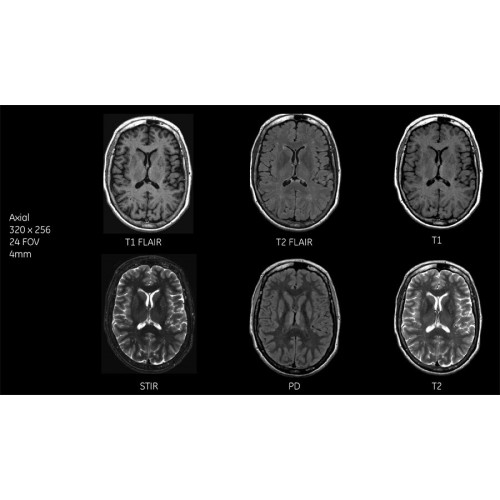

Детализация изображений

Система SIGNA Pioneer воплощает поразительные достижения в области визуализации. Передовая технология Total Digital Imaging (TDI) позволяет добиться большей четкости изображений и на четверть повысить соотношение сигнал/шум.

TDI построена на трех базовых компонентах:

• Технология Direct Digital Interface (DDI) использует независимый аналого-цифровой преобразователь для оцифровки сигнала от каждого из 97 радиочастотных каналов, что обеспечивает значительное увеличение качества за счет уменьшения фонового шума.

• Технология Digital Micro Switching (DMS) — это следующее поколение технологий радиочастотных катушек, основанное на замене аналоговых схем блокировки сверхбыстрыми микропереключателями (MEMS), что делает возможным быстрое переключение катушек для дальнейшего расширения возможностей визуализации с нулевым TE.

• Технология Digital Surround Technology (DST) — это новая технология объемной оцифровки данных, объединяющая сигналы от каждого элемента катушки. Прекрасное соотношение сигнал/шум и чувствительность поверхностных катушек в сочетании с превосходной однородностью и высокой проникающей способностью встроенной радиочастотной катушки — все это позволяет создавать качественные изображения не только позвоночника, но и всего тела.